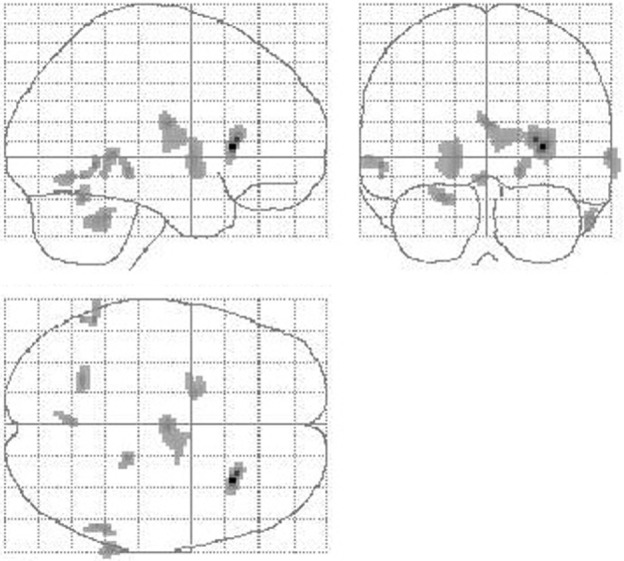

Figure 3.

Reduction of cerebral perfusion after DBS electrode placement during SHAM condition compared with preOP. An extended flow reduction was observed encompassing multiple areas within basal ganglia and thalamus (extent threshold k = 23 voxel).